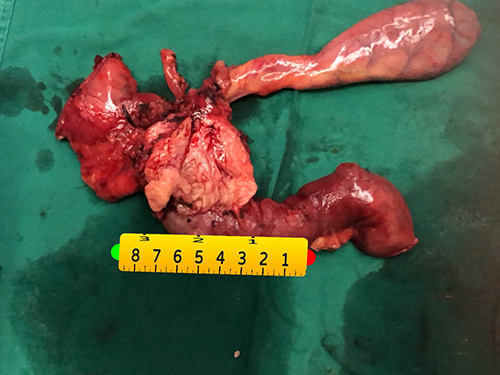

胰头癌-胰十二指肠切除